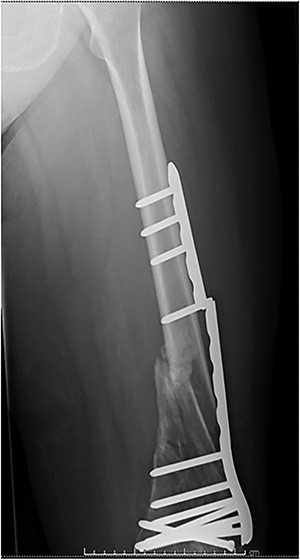

Case 4 (Figs 8–10): once again, screw placement too close to the fracture site has resulted in internal plate stresses exceeding its load-bearing capacity.

Inter-fragmentary screws have been utilized here. This lady may have benefited from placing an anterior bridging plate at the time of her original procedure if it was not possible to avoid this screw configuration.